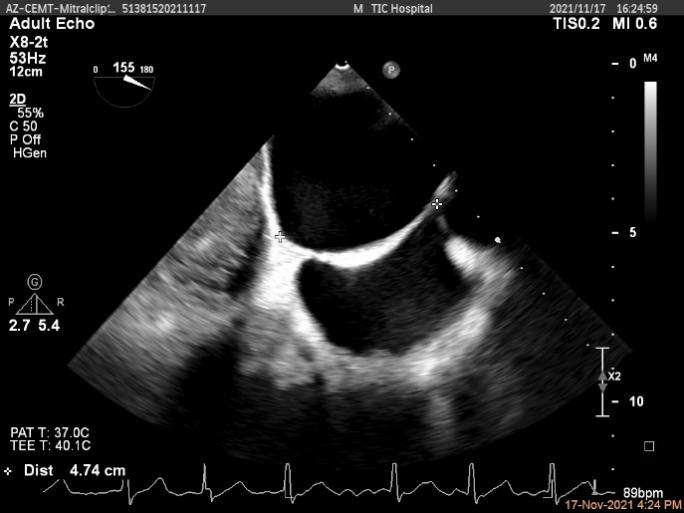

Qlab软件勾画估测瓣口面积约:6.52cm²